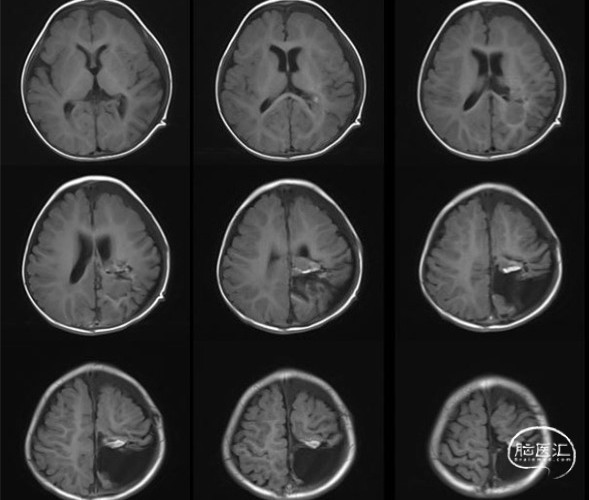

术前头部MRI平扫+增强示

左侧额顶枕叶巨大混杂信号肿块伴瘤内出血,呈明显不均匀强化:原始神经外胚层肿瘤?多形性胶质母细胞瘤?